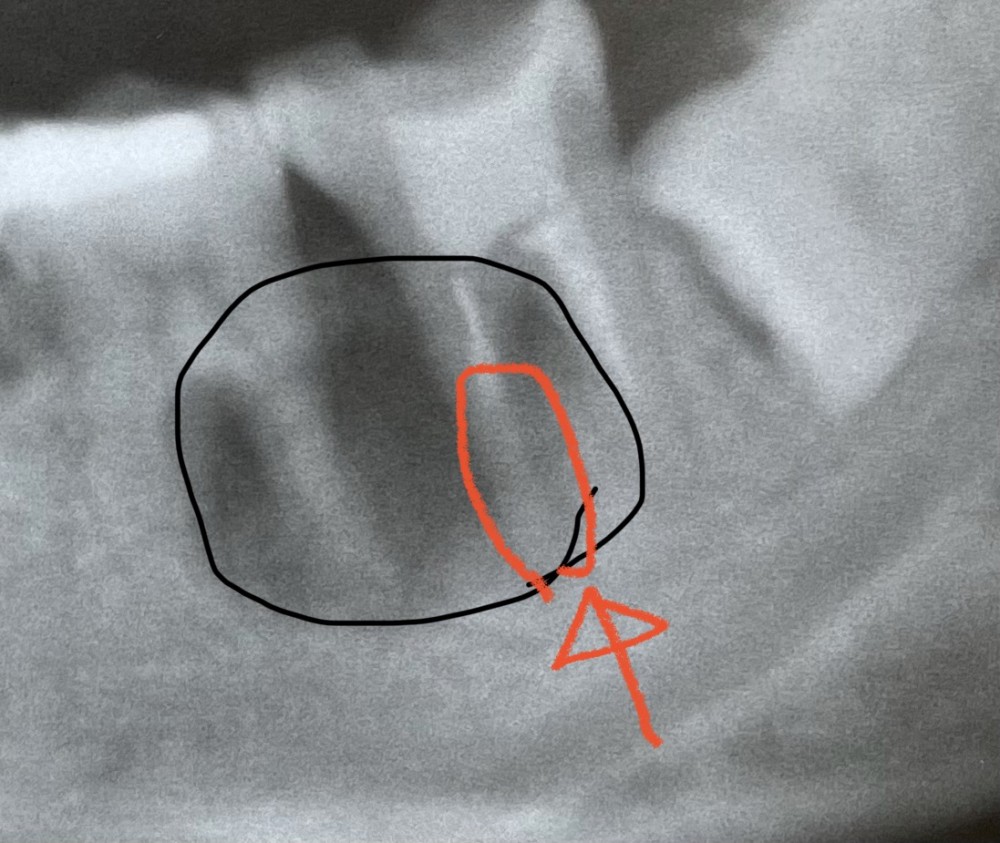

今回は、必要な検査をしたのち、オレンジ色で囲んだ部分にバイ菌が入り込んで病巣ができたと診断し、治療に取り掛かりました。

原因部分にお薬を注入したのを撮影したのが、下の写真です。

ここまで、初診時から1週間程度。

来院回数は2回です。

この時点で、歯茎の腫れ、歯の痛みは消失し、

患者さまは日常生活の不便は無くなりましたが、